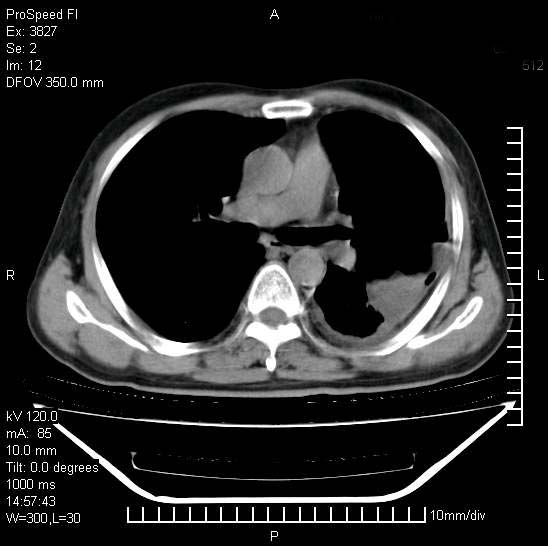

男性,一月前出现右侧肋区疼痛,较剧烈,干咳,无发热,自诉使用抗炎药后缓解,几天前又出现左侧剧烈疼痛,

发热,体温38。9,今天ct,考虑左侧包裹性脓胸,胸腔积液,右上中肺小斑片影,结核/炎症?胸水未见恶性细胞。